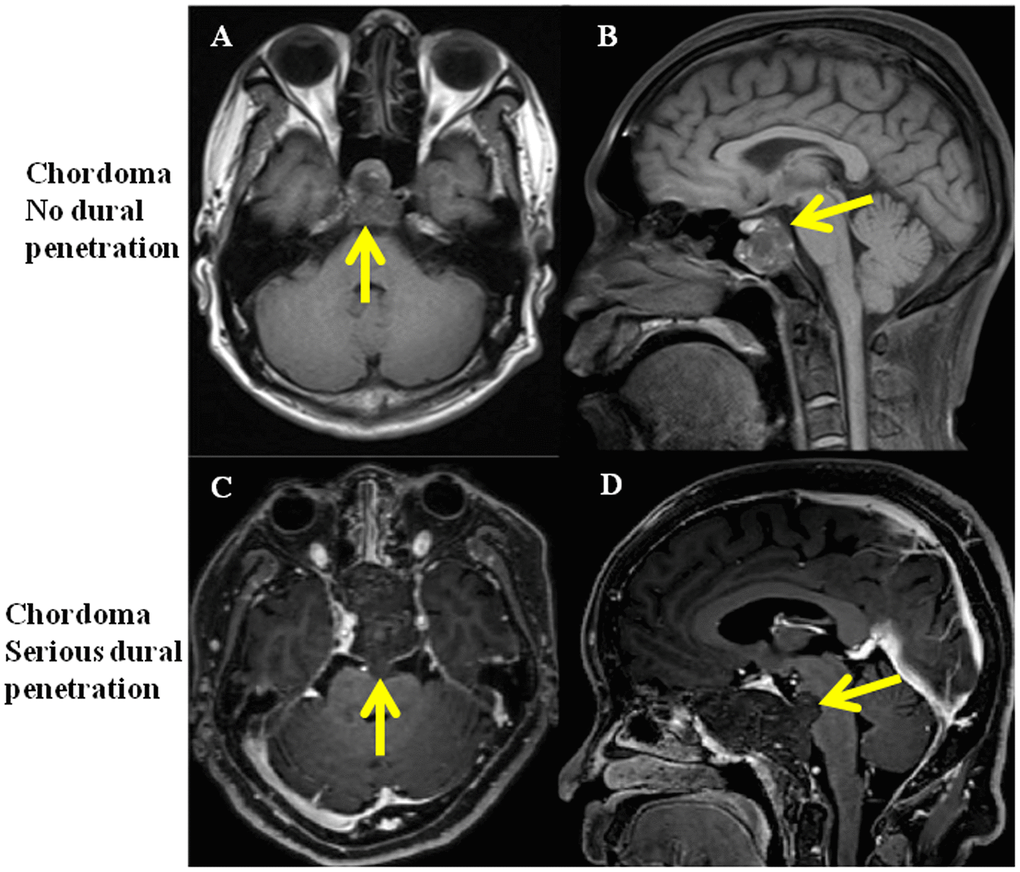

Twenty patients were enrolled in the study and were equally classified into no dural penetration group and serious dural penetration group. The tumor with no dural penetration demonstrated expansive growth, like a “bubble” in magnetic resonance imaging (MRI) and dural perforation was not found in surgical procedure (Figure 1A, 1B). In the chordomas samples with serious dural penetration, a bulge from the tumor into intracranial areas could be found in MRI, whereas dural perforation was found during the operation (Figure 1C, 1D). The patients’ demographic features were summarized in Table 1. The differences in age, sex and length of follow-up from surgery were not statistically significant between the two groups. However, the overall survival time and progression-free time were significantly differential, with poorer outcomes seen in the group with serious dural penetration (Figure 2A, 2B).

Figure 1. MRI of clival chordoma patients with no dural penetration and with serious dural penetration. (A, B) Same chordoma patient with no dural penetration, yellow arrows show the integrity of dura mater; (C, D) Same chordoma patient with serious dural penetration, yellow arrows show tumor penetrate the dura mater and invade into intracranial space.